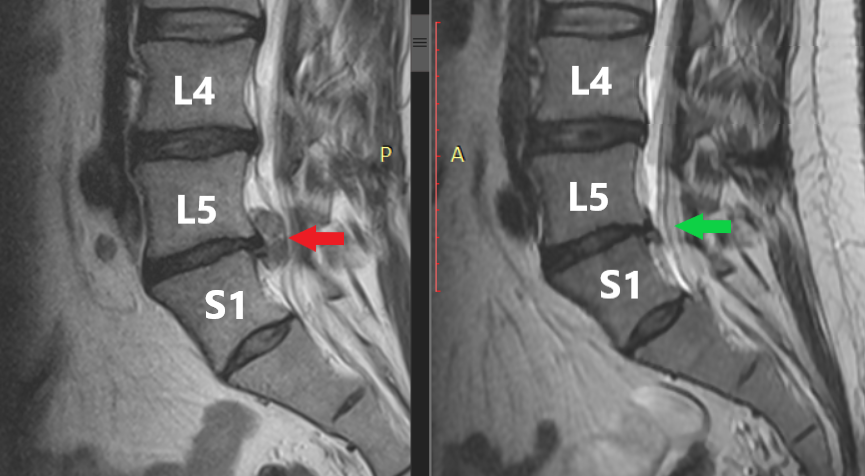

Rycina 1. Pozycycja strzałkowa. Po lewej (czerwona strzałka) przepuklina z istotnym częściowym sekwestrem L5-S1, po prawej (zielona strzałka) znaczna regresja przepukliny L5-S1 i całkowite wchłonięcie sekwestu.

Rycina 2. Przekrój poprzeczny. Po lewej (czerwona strzałka) widoczna przepuklina centralno-prawostronna z istotnym sekwestrem uciskającym struktury nerwowe. Po prawej (zielona strzałka) obraz po rehabilitacji – znaczna regresja przepukliny, swobodna przestrzeń w kanale kręgowym, brak istotnego ucisku.

Wielu pacjentów pyta: „czy każda przepuklina kręgosłupa może się sama wchłonąć?”. Odpowiedź brzmi: nie wszystkie, ale bardzo duża część – tak. Poniżej przedstawiam opis rezonansu mojego pacjenta któremu przepuklina i sekwestr uległy wchłonięciu – po lewej stronie znajduje się opis z przed rehabilitacji, a po prawej opis po rehabilitacji.